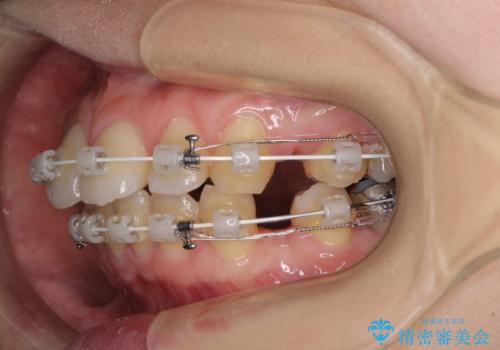

- 審美装置

- 2年5ヶ月

- 10-30回

上下左右第一小臼歯4本を抜歯し、ワイヤー装置にて口元を引っ込めるよう矯正治療を行うこととしました。